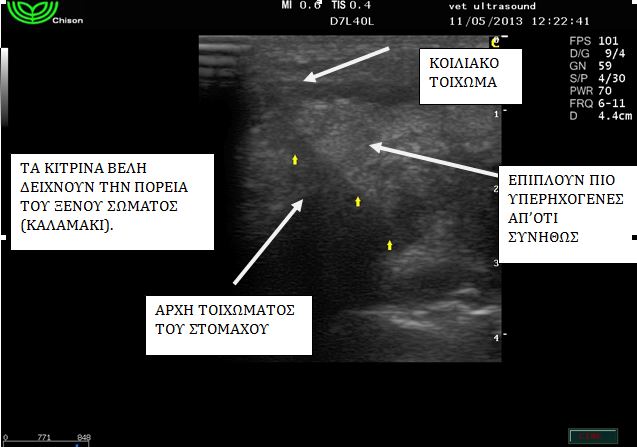

Στην υπερηχοτομογραφική εξέταση βρέθηκε ξένο σώμα το οποίο ξεκινούσε από το στομάχο και πρόβαλε κάτω από το δέρμα.